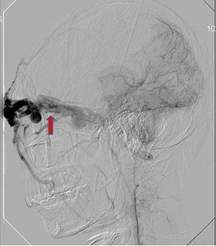

1、腦血管造影間接型頸動脈海綿竇瘺腦血管造影檢查的目的是確定瘺口的位置,供血動脈,靜脈引流形式,有無頸外動脈系統與頸內動脈系統和椎動脈系統的“危險吻合”等。腦血管造影檢查的內容包括患側頸內動脈的選擇造影,患側的椎動脈,頜內動脈,咽升動脈造影和對側頸內動脈和頸外動脈的選擇造影。微導管超選擇造影可進一步了解各供血動脈的供血情況。正常情況下,海綿竇接受眼上、下靜脈和蝶頂竇的引流,再經岩上、下竇引流到橫-乙狀竇交界處和頸靜脈球。兩側的海綿竇經海綿間竇相交通。在CCF存在的情況下,海綿竇內壓力增高,血流方向發生改變:經眼上靜脈逆流入角靜脈和面靜脈,經海綿間竇注入對側海綿竇,以及逆流入蝶頂竇等。此類頸動脈海綿竇瘺的供血情況通常非常複雜。在經動脈途徑栓塞治療前,必須仔細研究腦血管造影,特別注意有無“危險吻合”的存在。頸總動脈分叉處的情況也是腦血管造影要觀察的重要內容。如果該處有動脈粥樣硬化斑塊,則禁止採用壓迫頸總動脈的方法治療間接型頸動脈海綿竇瘺。